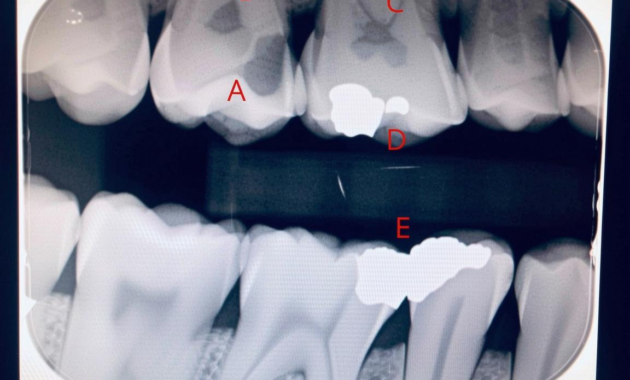

X-rays operate on a simple yet ingenious principle: different substances absorb radiation at varying rates. Teeth, being dense and calcified structures, appear prominently on X-ray films, often as white or light gray areas. However, the presence of cavities introduces a distinct contrast. When a cavity forms, it represents a loss of mineral content in the tooth, resulting in an area that absorbs less radiation than the surrounding healthy tooth structure. Consequently, these areas manifest as dark spots or shadows on the X-ray.

The appearance of a cavity on a dental X-ray can vary depending on its progression. Early-stage cavities may initially show up as subtle, smudgy areas of radiolucency—dark patches that may not draw immediate attention. As the decay advances, the shadows become more pronounced and larger, indicating a deeper invasion into the tooth’s anatomy. Dentists often categorize cavities based on their depth, where Class I lesions are confined to the pits and fissures of teeth, whereas Class II involves the proximal surfaces, and more severe cases penetrate the pulpal region.

Moreover, it’s not just the shape or darkness of a cavity that provides diagnostic clues. The location of the cavity is equally telling. Cavities often form in specific areas where plaque tends to accumulate. These include the fissures of the molars—those deep grooves designed for grinding food—and the interproximal areas between teeth, where toothbrush bristles may fail to reach. On an X-ray, a dentist can discern these common locations, which inform strategies for preventive treatment and patient education.